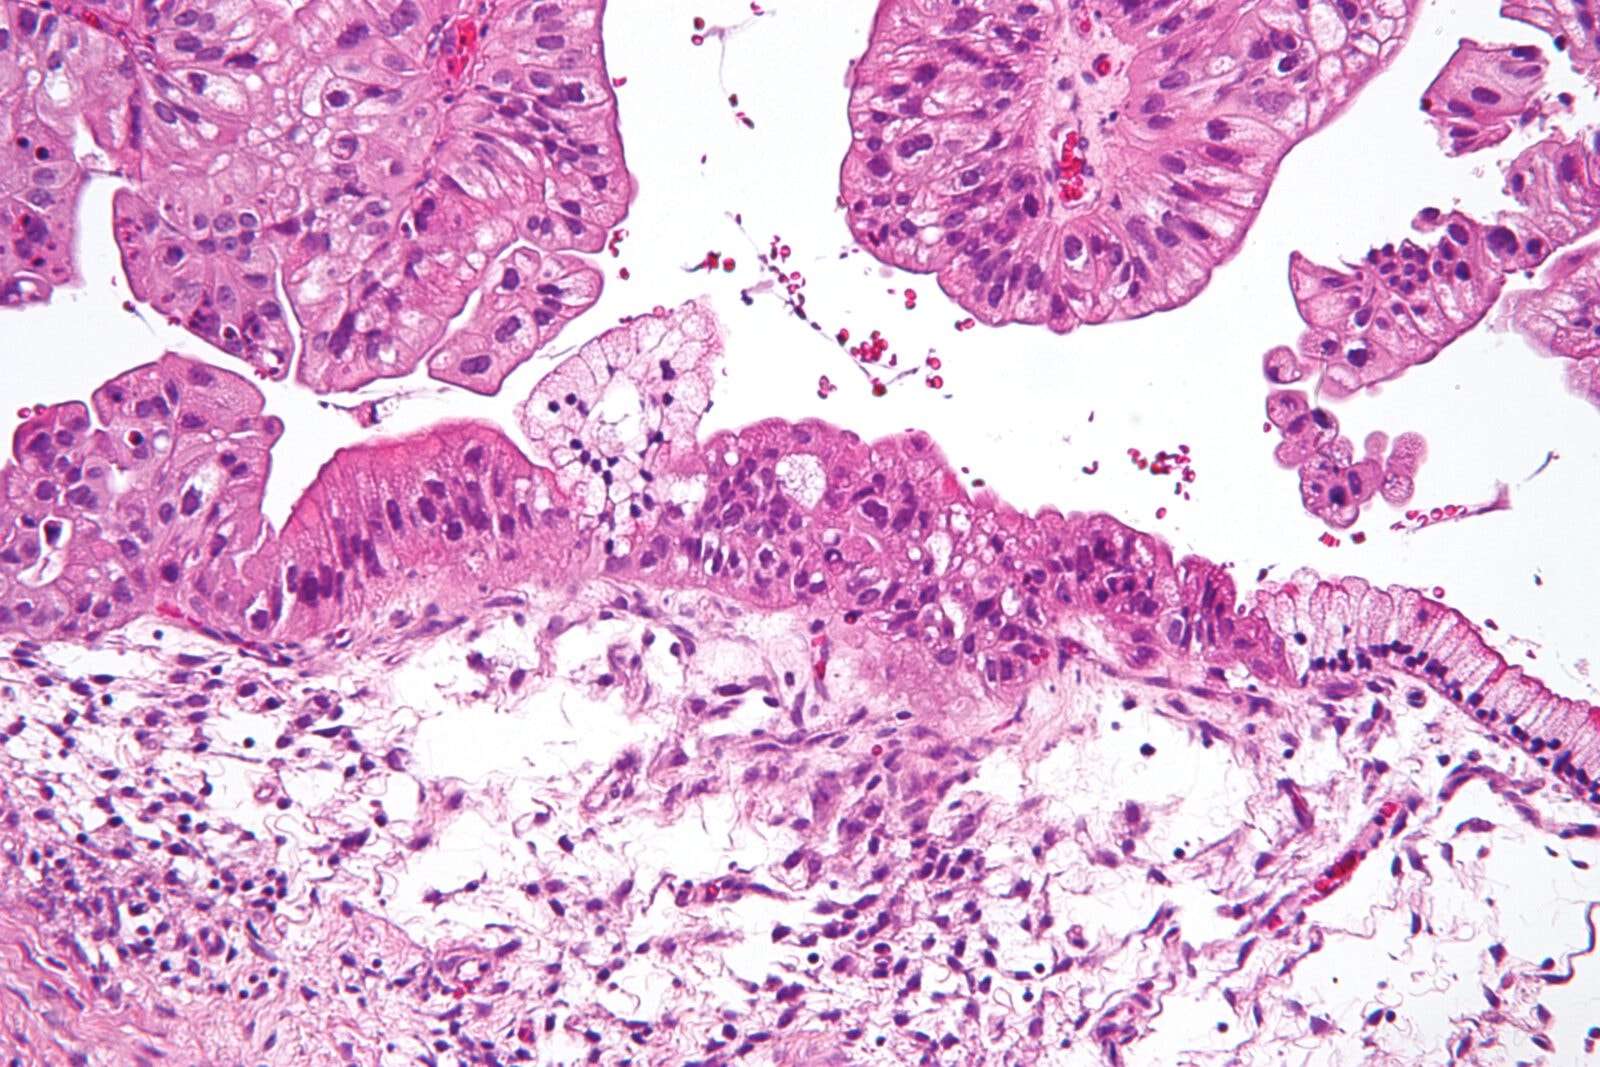

“Ciekła biopsja” okazała się najbardziej trafna w wykrywaniu raka jajnika, wątroby, trzustki oraz pęcherzyka żółciowego. Diagnoza okazywała się trafna u czterech na pięciu pacjentów.

Niewiele mniejszą dokładność zaobserwowano w wykrywaniu chłoniaka (77%) oraz szpiczaka (73%). Rak jelit wykrywany był trafnie u dwóch na trzech pacjentów, rak płuc u 59%, nowotwory głowy i szyi w 56%. To zatem jeszcze nie koniec prac nad metodą, naukowcy zapowiadają kontynuację prac. Dodają, że wielką zaletą “ciekłej biopsji” jest to, że można jej poddać praktycznie każdego, bez ryzyka.